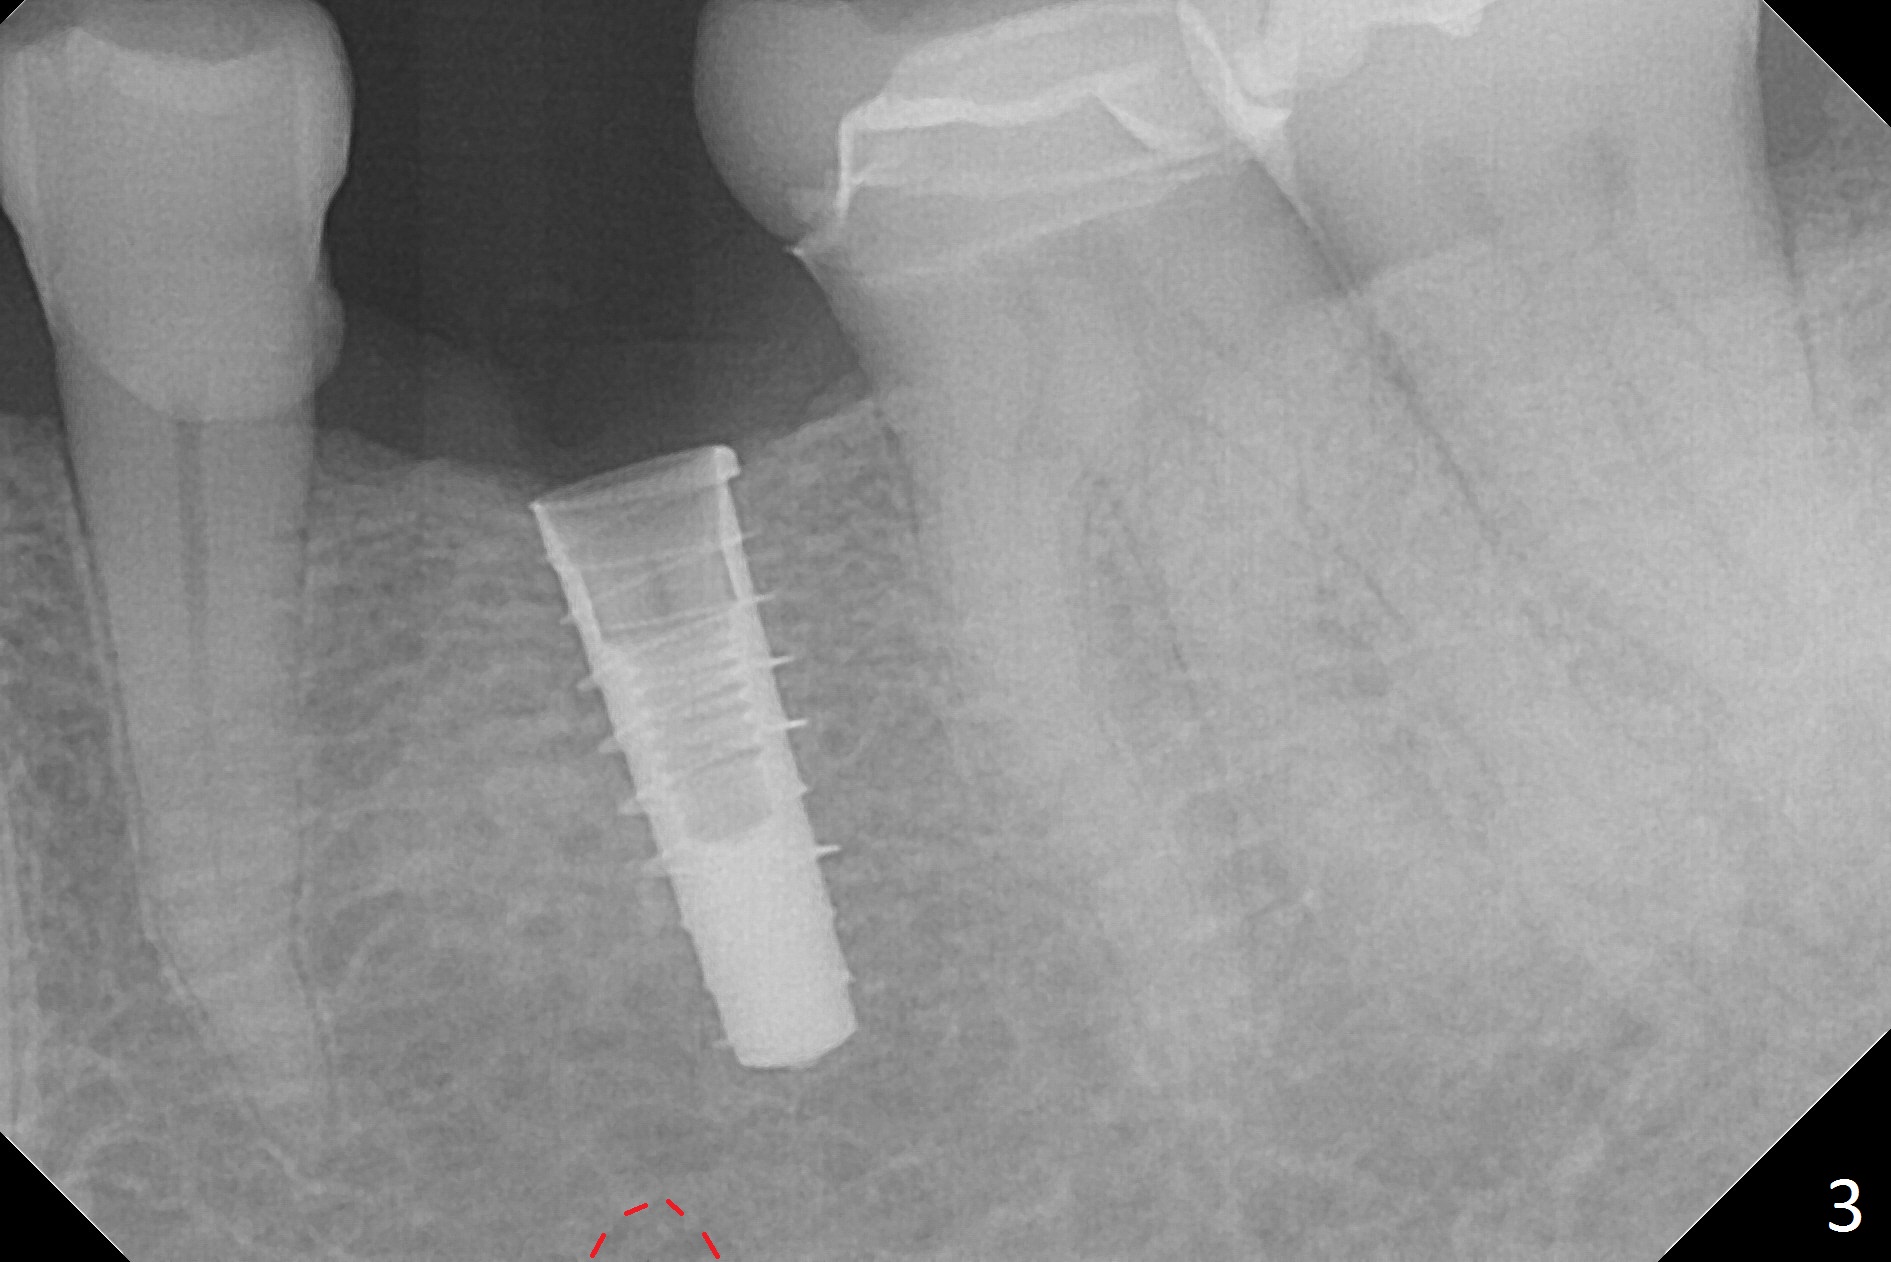

Initial osteotomy with 1.6 mm drill for 11 mm seems to be distal (Fig.1).  The trajectory should be changed as shown by the black line in Fig.2; the drawback would be close to the Mental Loop (red line).  Fortunately the trajectory is changed, but not so much as to be close the Loop when a 4x11 mm dummy implant is placed (Fig.3).   When a 4x13 mm IBS is placed with 46 Ncm, there is clearance from the Loop (Fig.4-6).  In fact there is no postop paresthesia.  The main point is no block anesthesia.  Infiltration anesthesia is administered with 34 mg Xylocaine with 17 mcg Epinephrine.  The patient experiences dull pain when the implant is placed (Fig.4-6).  After further anesthesia with 68 mg Septocaine, 17 mcg Epinephrine, the implant is torqued for a few turns (still with some discomfort).  Finally autogenous bone with Osteogen is placed around the implant following placement of a 4.5x4(2) mm abutment.  To reduce anxiety, a shorter implant should have been used. The patient complains of cold sensitivity in the lower left quadrant 4 months postop (Fig.7): the implant apparently close to the Mental Loop.  Without an immediate provisional, the gingiva around the abutment is healthy.